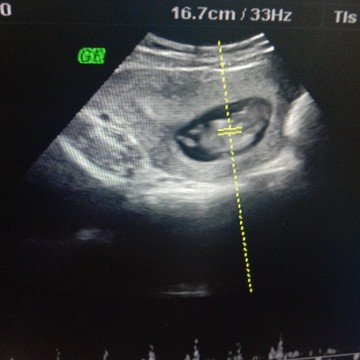

ตอนซาวด์ 11+5W พอได้ยินเสียงหัวใจน้องเต้นแล้วอยากเจอหน้าไวไวจัง 😍😍😍 อันนี้คือรีบหันหลังให้แม่เลยนะลูก งอลอะไรแม่รึป่าว 😄😂